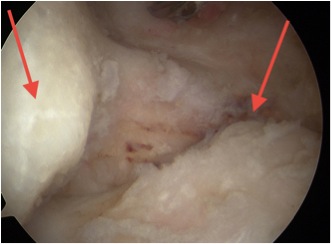

Arthroscopy

Chondral damage capitellum Chondral damage radial head Chondral damage ulnohumeral joint

Post elbow fracture malunion / posterior impingement / FFD 40o

Posterior elbow arthroscopy, with arrows pointing to olecronon tip on the right in the flexed and extended position